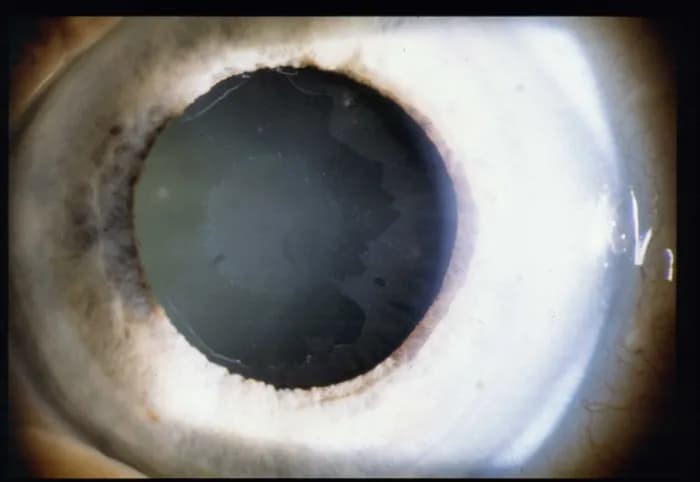

Sprawdź, czy masz jaskrę! Poznaj objawy i kluczowe badania, które pomogą w wczesnej diagnozie i ochronie wzroku.

Poznaj najważniejsze objawy jaskry barwnikowej i dowiedz się, jak je rozpoznać, aby skutecznie chronić swój wzrok przed poważnymi problemami.